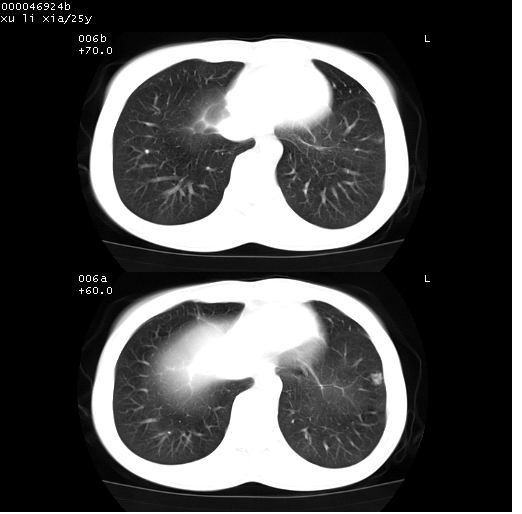

患者 女,25岁。因“左侧卵巢肿瘤”术前胸片偶然发现两肺病变。平素无明显不适,无呼吸系统症状及体征,无传染病史。

盆腔ct扫描(ps+ce)提示:左侧附件区畸胎瘤。

临床诊断:1)左侧卵巢肿瘤。2)两肺感染性病变。

胸部ct轴位平扫(层厚10mm,螺距1.5,重建间隔10mm),图像如下:

(注:上级医院会诊胸部ct片——考虑为肺部真菌感染。)

病灶呈地图样分布于肺外围,与正常组织分界清晰+弥漫性磨玻璃影中见小叶间隔增厚呈碎石路样表现+年轻女性,无明显临床症状=肺泡蛋白沉积症?

双肺上叶可见节段性渗出性病变,可见树芽征像,左肺下叶背段可见结节影。